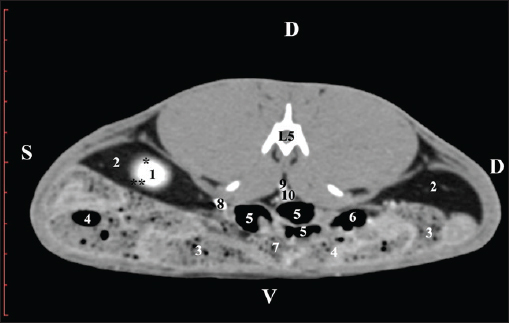

The pre-contrast anatomical scan at the L4 level provided data about the location of the renal pelvis within the renal sinus. The initial part of the pelvis renalis appeared as a distinct funnel-shaped hypoattenuated soft tissue, whose central part was widened and formed the recessus renalis. The transition of the narrowed end of the renal pelvis into the hypoattenuated left ureter was without a sharp boundary. The left kidney was in contact with the cecum, colon ascendens, and colon transversum ventrally. Crista renalis was observed as a hypoattenuated linear soft tissue finding (Figs. 10 and 11).

Fig. 10. Pre-contrast computed tomography (CT) anatomical scan of the regio-abdominis media at the cranial L4 edge level. (1) Ren sinister; (2) pelvis renalis and crista renalis; (3) ureter; (4) cecum; (5) colon ascendens; (6) colon transversum; (7) colon descendens; (8) adipose collections.

Fig. 11. Pre-contrast computed tomography (CT) anatomical scan of the regio-abdominis media at the caudal L4 edge level. (1) Ren sinister; (2) pelvis renalis; (3) ureter; (4) adipose collections; (5) cecum; (6) colon ascendens; (7) colon transversum; (8) colon descendens; (9) mesenterium; (white arrows) recessus renalis; (*) crista renalis.